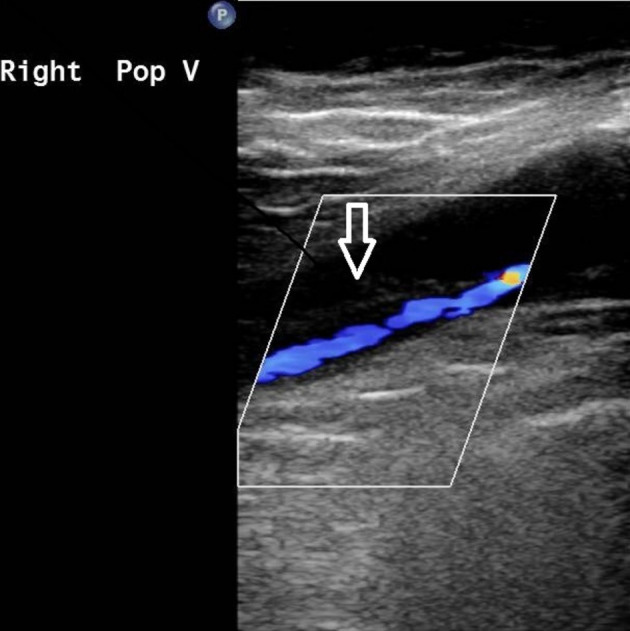

‘To further survey the pulmonary embolism, we conducted examinations in order to verify the possible etiology, including autoimmune disease markers (including antinuclear antibody, C3, C4, lupus anticoagulant, anticardiolipin immunoglobulin), tumor markers (including CEA, alpha-fetal protein, CA199, and PSA), coagulant function tests (including protein C function, antithrombin III, prothrombin time, partial thromboplastin time), all of which were within normal limits. Protein S function was 25.4% (normal value 62.6-150.4%) and the anti-platelet factor 4 (PF4) antibody titer was 50.01 ng/ml (cutoff value of 50 ng/ml) with an optical density of 0.424 units (weakly positive, cutoff value of 0.4 units). Left popliteal vein thrombosis was found by peripheral Doppler sonography.’

Peripheral Doppler revealed probable thrombus with partial occlusion at the right popliteal vein (white open arrow).